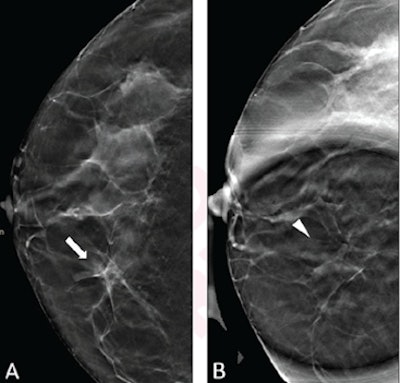

While research suggests that DBT and digital mammography are on equal ground when it comes to spot compression viewing of equivocal findings in diagnostic settings, findings may still be indeterminate when it comes to benign asymmetries. Research also suggests that it may still be difficult for spot compression DBT to find differences between subtle architectural distortion and normal breast tissue, especially in women with dense breasts.

Deleau et al wrote that this view could make small lesions more noticeable and allow for a lesion's morphologic features to be better assessed. This, in turn, helps with the radiologist's confidence in differentiating masses, architectural distortion, and asymmetries.

"For example, the radiologist may have a heightened level of suspicion in the presence of a possible architectural distortion if the finding persists on the DBT spot compression view," they added.